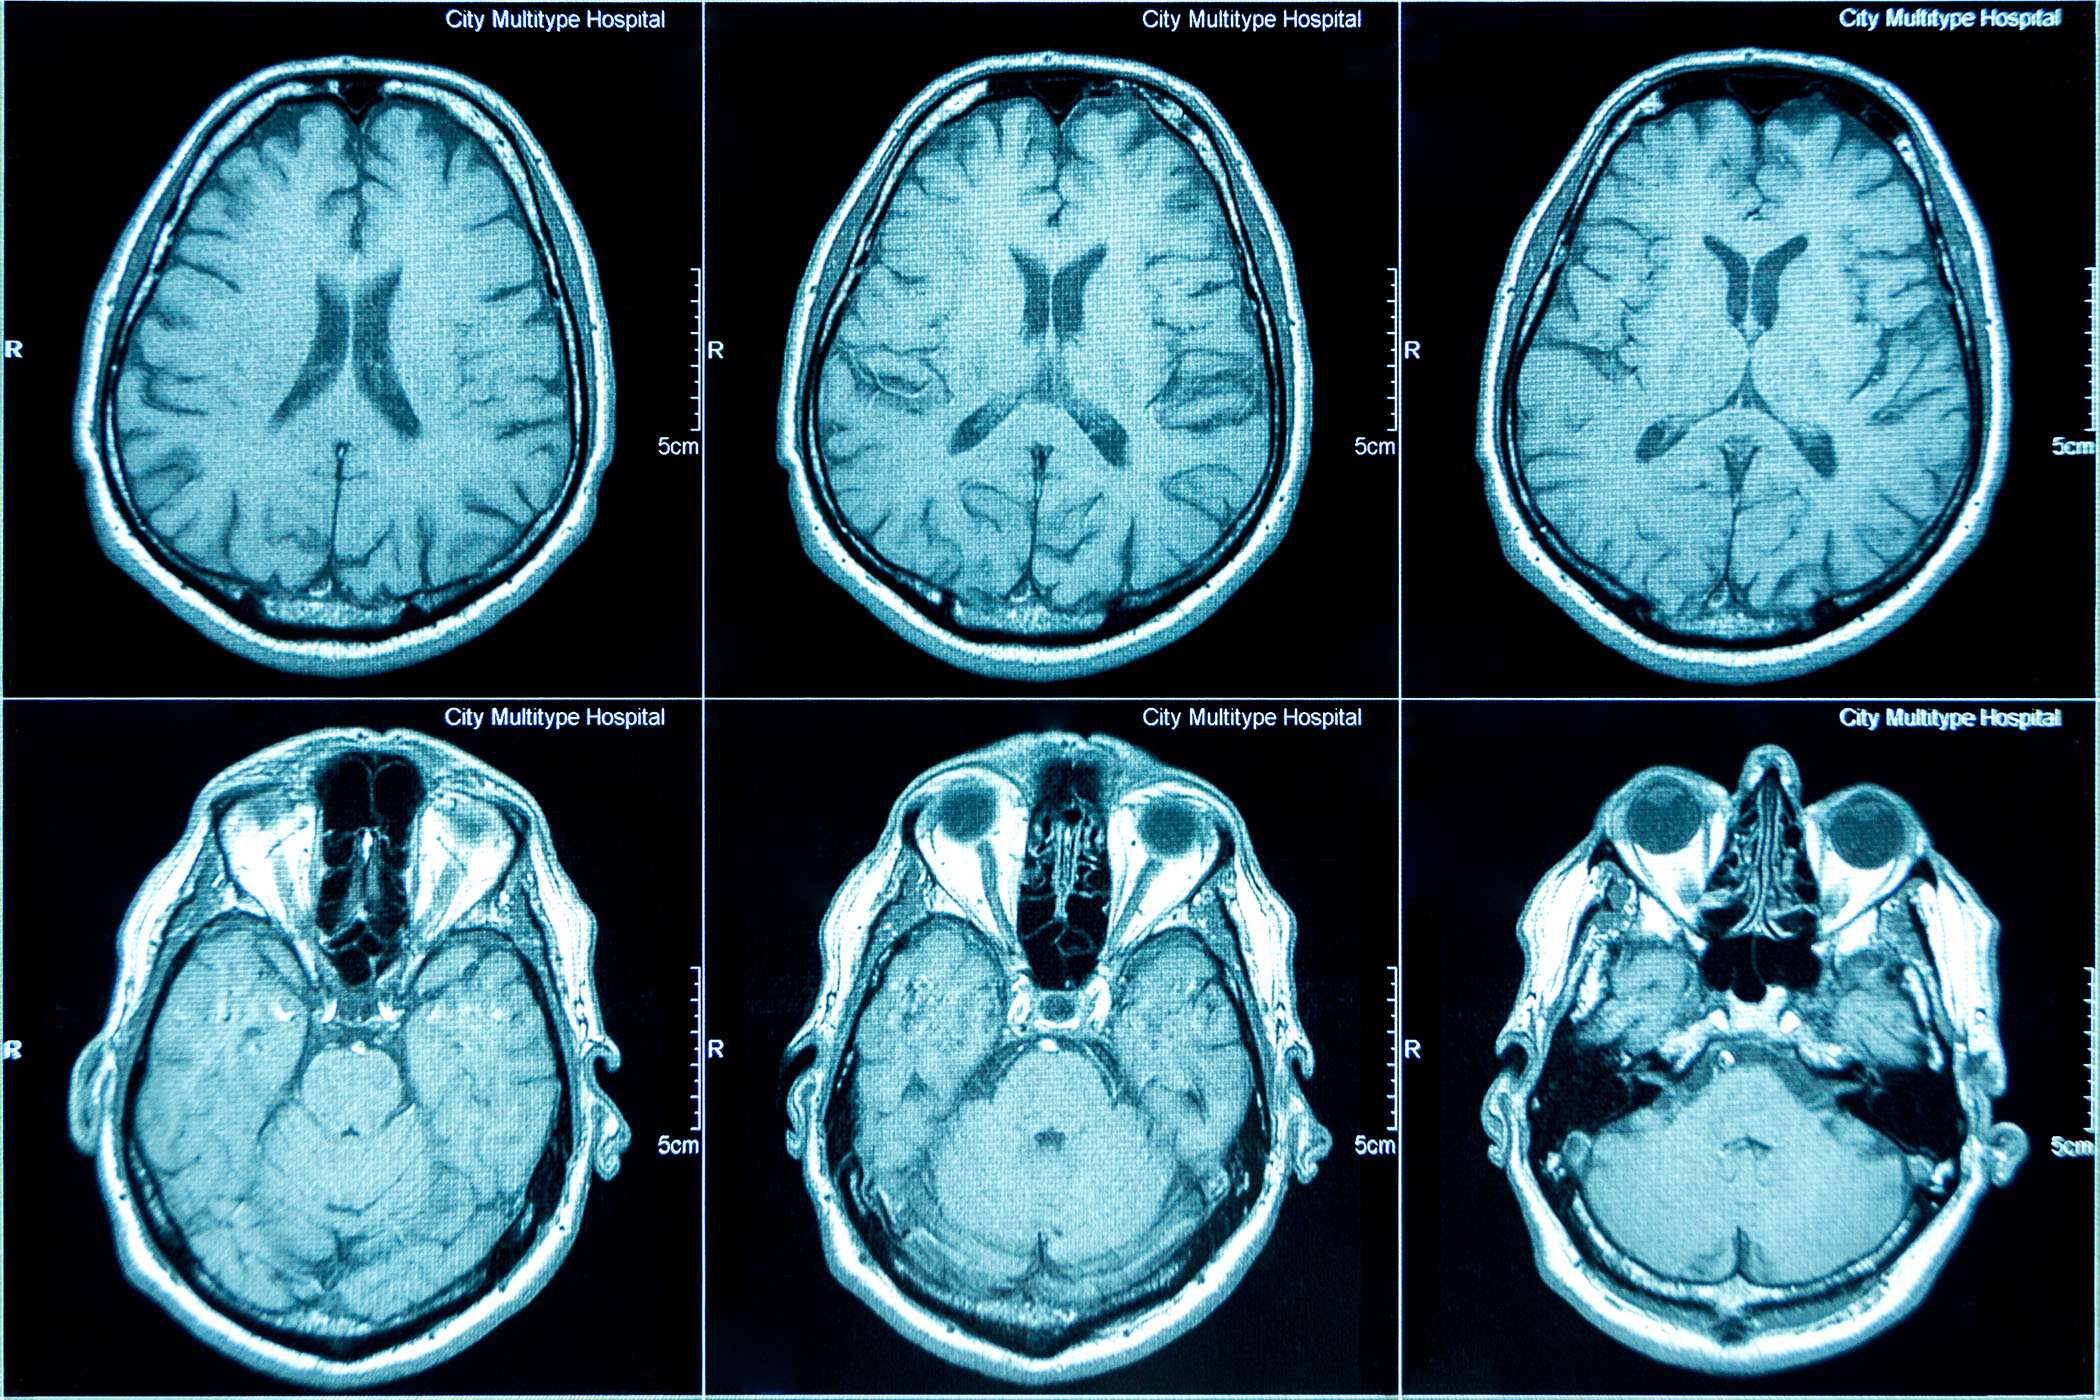

Researchers at Rutgers Business School, in a first-time collaboration with the Center for Advanced Human Brain Imaging Research at the Rutgers Brain Health Institute, used an MRI scanner to find out.

While magnetic resonance imaging, a noninvasive diagnostic procedure, is most often used for clinical or basic cognitive neuroscience, Rutgers researchers used an MRI scanner in a pilot grant program to study brain responses in third-party observers witnessing abusive supervision. The program and technical assistance allowed researchers to adapt it for real-time observation of emotional and moral processes in a workplace context.

Participants watched video scenarios depicting verbal abusive supervision across academic, sports and business contexts during MRI scanning, allowing direct measurement of neural activity that complements typical behavioral or survey-based approaches.

Pham and colleagues used functional MRI to examine what happens in the brain when individuals witness abusive supervision, which is defined as the extent to which supervisors engage in the sustained display of hostile verbal and nonverbal behaviors by organizational scholars.

The study also highlights how advanced brain-imaging resources at Rutgers can support interdisciplinary collaborations beyond conventional neuroscience fields. The Center for Advanced Human Brain Imaging Research houses an MRI scanner dedicated to research and provides technical support for task design, sequence optimization, data analysis, pilot scanning programs and workshops.